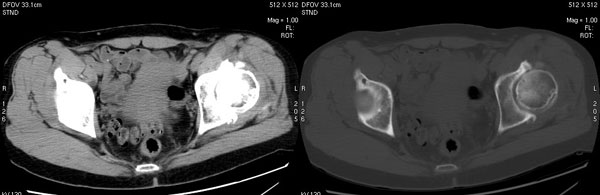

以下是引用jiajie在2006-7-14 17:19:00的发言:[br]ct所见:双侧髋关节不对称,左侧关节间隙变窄,关节面毛糙。左侧股骨头变形、无明显变小,前上缘与髋臼融合,融合处骨质明显增生硬化,并见数个小囊变影。股骨头下端与股骨颈交界部见囊样变,邻近肌肉内见囊样密度减低区,ct值24hu。右侧髋关节形态未见异常。[br][br]ct诊断:左侧髋关节结核可能,请结合临床资料进一步分析。

以下是引用lihuuuu在2006-12-5 10:14:00的发言:[br]定位像示:左侧髋臼变浅,倾斜度加大,髋臼外上缘呈波浪状不规则,骨质增生硬化,髋关节上缘间隙明显变窄,股骨头向外上轻度移位。轴位像示:左侧股骨头变形,前上缘与髋臼融合,融合处骨质明显增生硬化,并见数个小囊变影。股骨头下端与股骨颈交界部见囊样变,邻近肌肉内见密度减低区,ct值24hu,内缘见弧形高密度钙化影。右侧髋关节形态未见异常。[br]ct诊断:左侧髋臼发育不良[br] 左侧股骨头缺血性坏死[br] 左侧肌肉内低密度影伴有高密度钙化-考虑早期骨化性肌炎[br] [br]“我认为在描述上已经写了肌肉部分,印象诊断里应该写主见”[br]